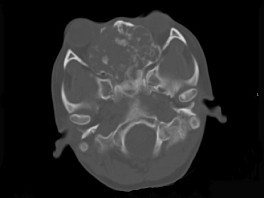

男性,28岁,因鼻塞、头痛1年余,鼻窦CT扫描如图所示,请选择正确的描述与结论()

A.双侧上颌窦、筛窦、鼻腔及蝶窦内见软组织肿块影

B.肿块内密度不均,有较多致密钙化影

C.窦壁及颅底骨质破坏

D.考虑鼻窦骨瘤

E.考虑为鼻窦软骨瘤

[多选题]男性,28岁,因鼻塞、头痛1年余,鼻窦CT扫描如图所示,请选择正确的描述与结论()A.双侧上颌窦、筛窦、鼻腔及蝶窦内见软组织肿块影B.肿块内密度不均,

[多选题]男性,28岁,因鼻塞、头痛1年余,鼻窦CT扫描如图所示,请选择正确的描述与结论()A.双侧上颌窦、筛窦、鼻腔及蝶窦内见软组织肿块影B.肿块内密度不均,

[多选题]男性,28岁,因鼻塞、头痛1年余,鼻窦CT扫描如图所示,请选择正确的描述与结论()A.双侧上颌窦、筛窦、鼻腔及蝶窦内见软组织肿块影B.肿块内密度不均,

[多选题] 男性,28岁,因鼻塞、头痛1年余,鼻窦CT扫描如图所示,请选择正确的描述与结论()。A . 双侧上颌窦、筛窦、鼻腔及蝶窦内见软组织肿块影B . 肿块内密度不均,有较多致密钙化影C . 窦壁及颅底骨质破坏D . 考虑鼻窦骨瘤E . 考虑为鼻窦软骨瘤

[多选题] 男性,28岁,因鼻塞、头痛1年余,鼻窦CT扫描如图所示,请选择正确的描述与结论()A .双侧上颌窦、筛窦、鼻腔及蝶窦内见软组织肿块影B .肿块内密度不均,有较多致密钙化影C .窦壁及颅底骨质破坏D .考虑鼻窦骨瘤E .考虑为鼻窦软骨瘤